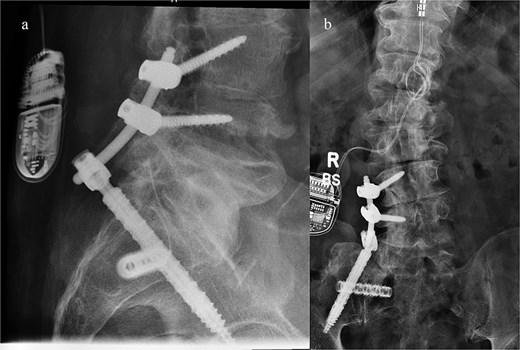

A CT of the pelvis showed significant hyperostosis along the anterior right SI joint and a pseudoarthrosis between the L5 transverse process and the sacral ala that was osteoblastic-appearing in nature (Fig. 1). A SPECT-CT demonstrated increased uptake along the same area, suggestive of inflammatory degenerative changes (Fig. 2).

Coronal (left) and axial (right) views of pelvic CT-SPECT highlighted increased uptake along the right SI joint, suggestive of inflammation (arrows).